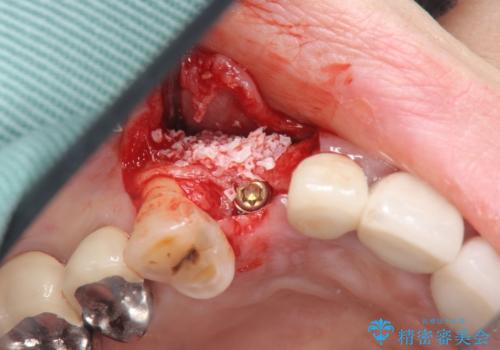

- 45万円(ストローマンインプラント・骨造成・チタンカスタムアバットメント・ジルコニアクラウン)費用は治療当時の料金となります

前歯のインプラントを仕上げるには骨や歯ぐきの条件を整えることが肝要です。